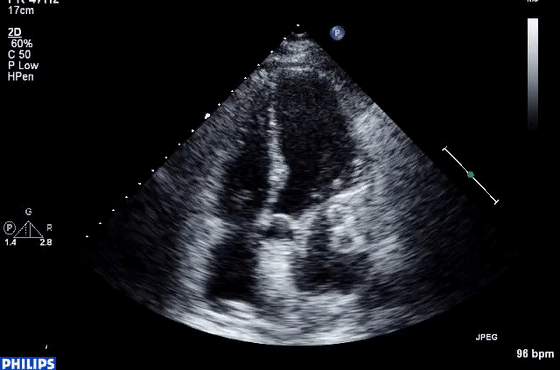

7、近场杂波

由于探头换能器本身的高振幅振荡,近场结构有时会被遮蔽,造成所谓的近场杂波。这在怀疑有心尖室血栓的病例中尤其重要(图7,视频10)。谐波成像的引入和换能器设计技术的进步已经减少了这种伪影的发生。

图7 心尖四腔视图中的近场杂波(箭头),疑似心尖血栓。(视频10)显示正常的心尖心肌动力学,杂乱回波和心肌运动之间没有关系。